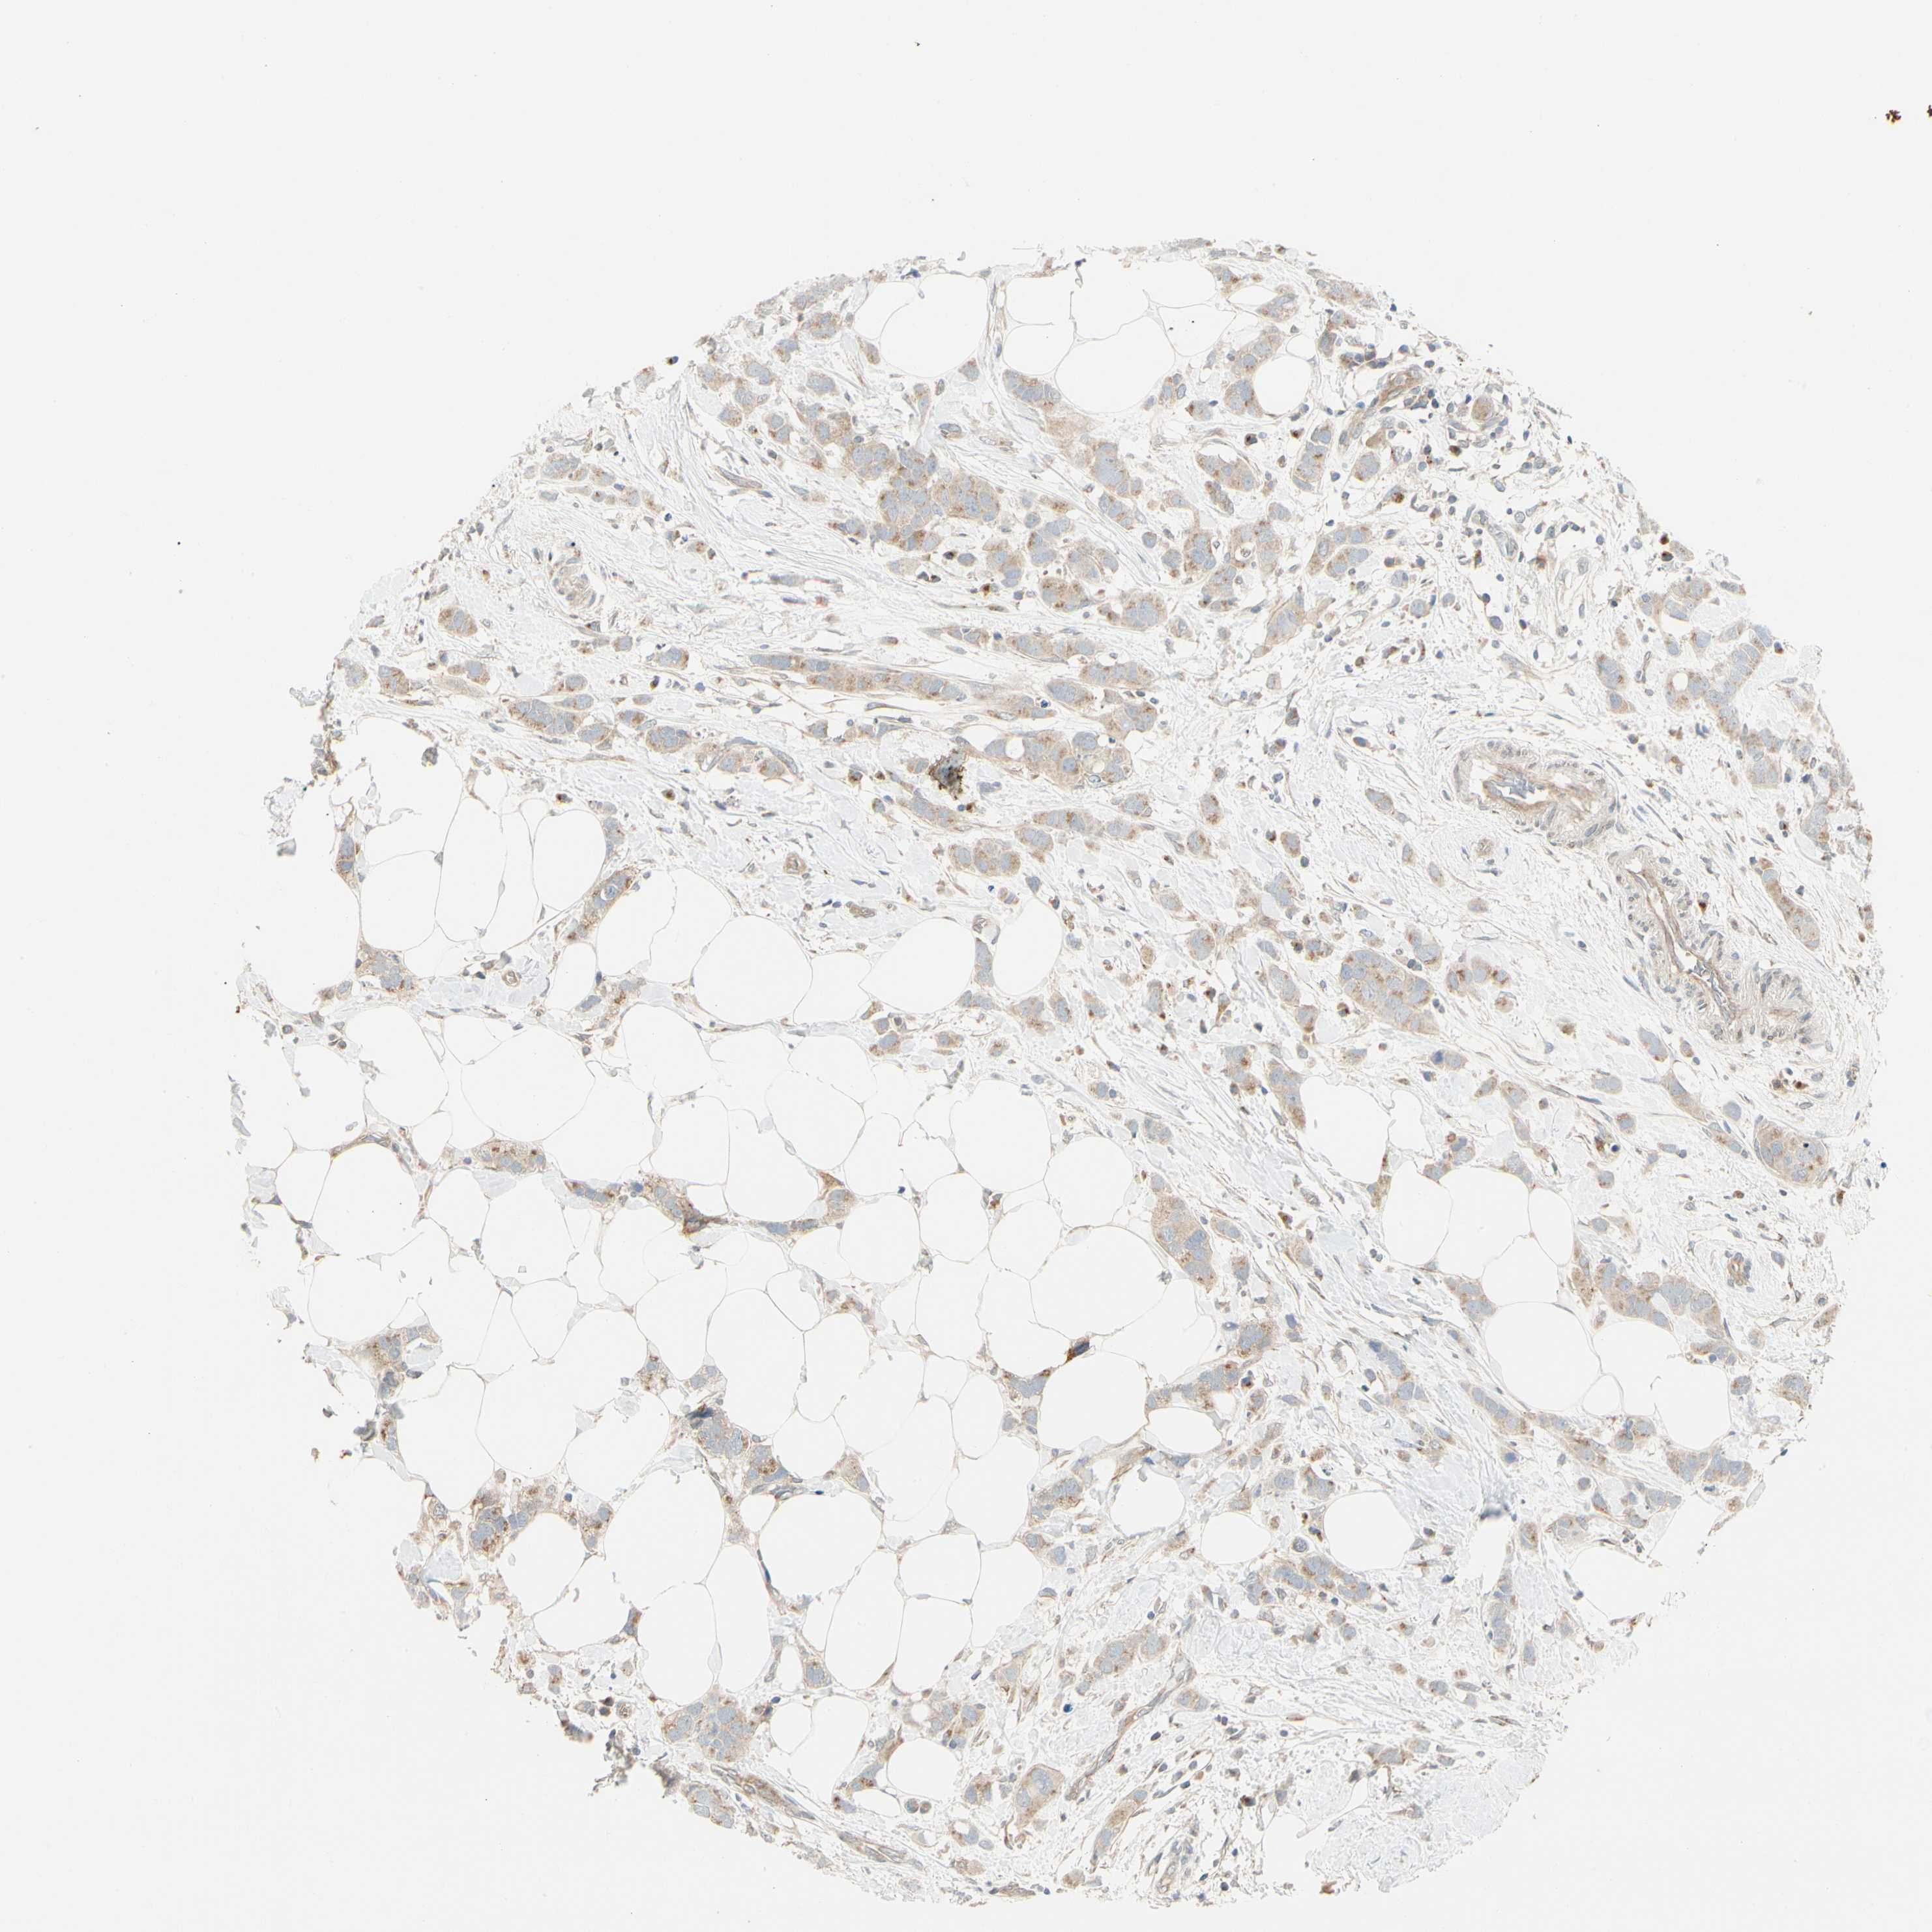

CANCER BREAST CANCER Show tissue menu

BRCA TCGA BRCA VALIDATION PROTEIN EXPRESSION